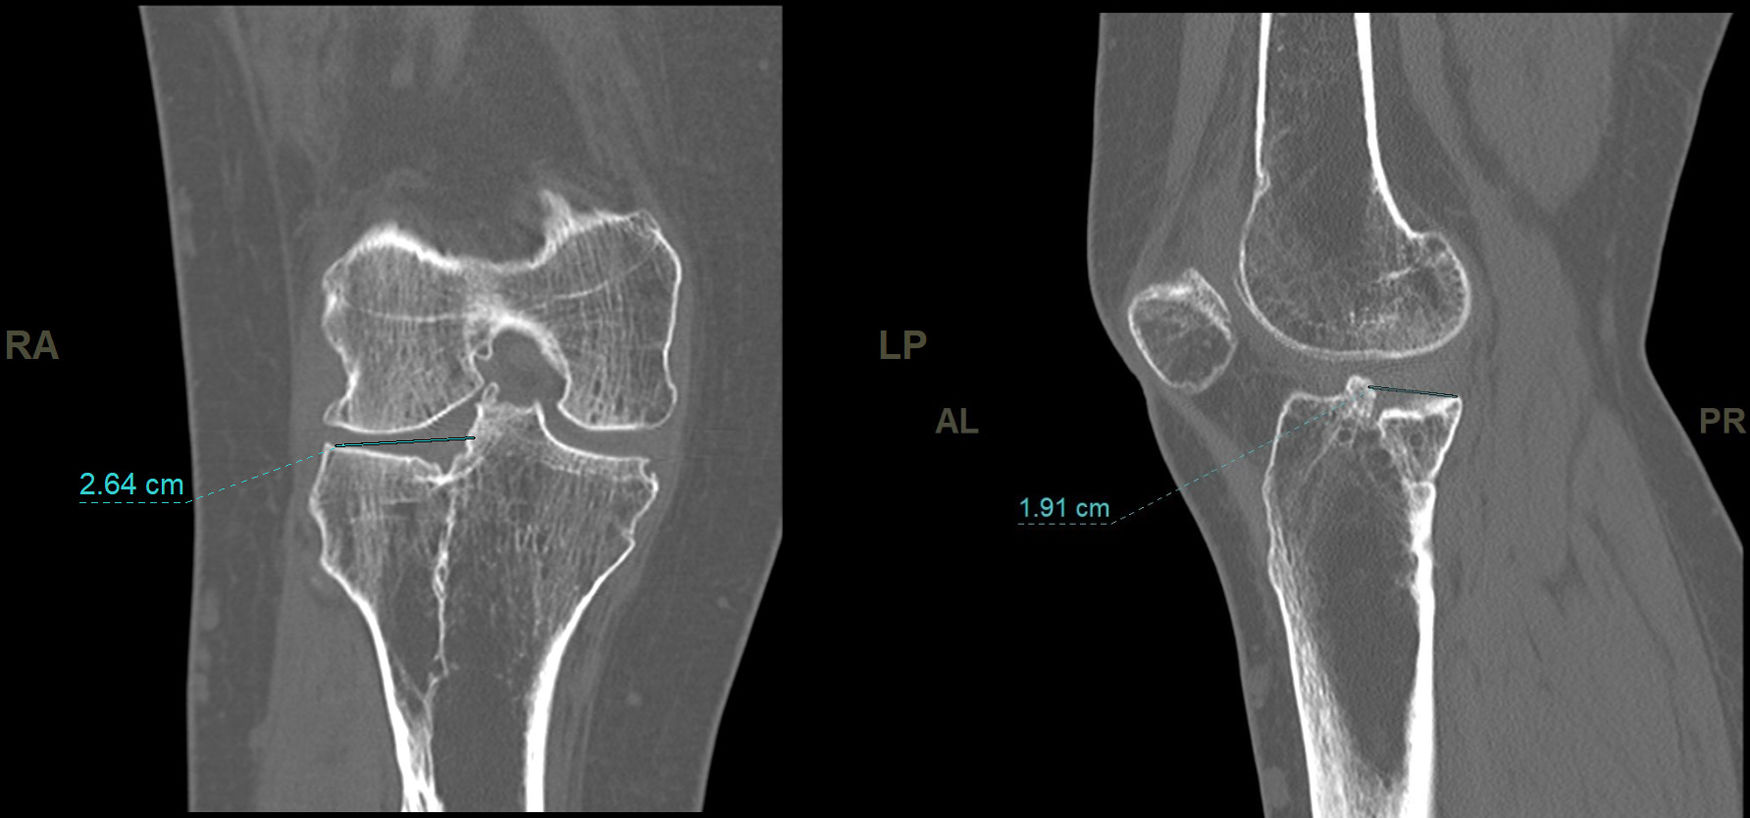

In the CT study, volumetric acquisition was performed using a multi-slice scanner at .6mm thickness, followed by multiplanar reconstruction at 1.5mm slice intervals. In coronal plane reconstruction, the point of greatest fracture depression in millimetres, corresponding to the maximum joint step, and the maximum width/transverse diameter in millimetres were analysed. In the sagittal plane, the maximum anteroposterior joint step diameter in millimetres and the maximum external tibial plateau slope in degrees were measured (Fig. 3). Post-processing in the axial plane involved delimiting the fracture contour and calculating the affected area in cm2, as well as determining the maximum anteroposterior and transverse diameters in mm (Fig. 4).

The mean step measured on CT was 3.6mm (SD: 1.9mm). The mean area measured on CT was 17.57cm2 (SD: 6.1cm2). The mean slope was 12.3 degrees (SD: 5.3 degrees).